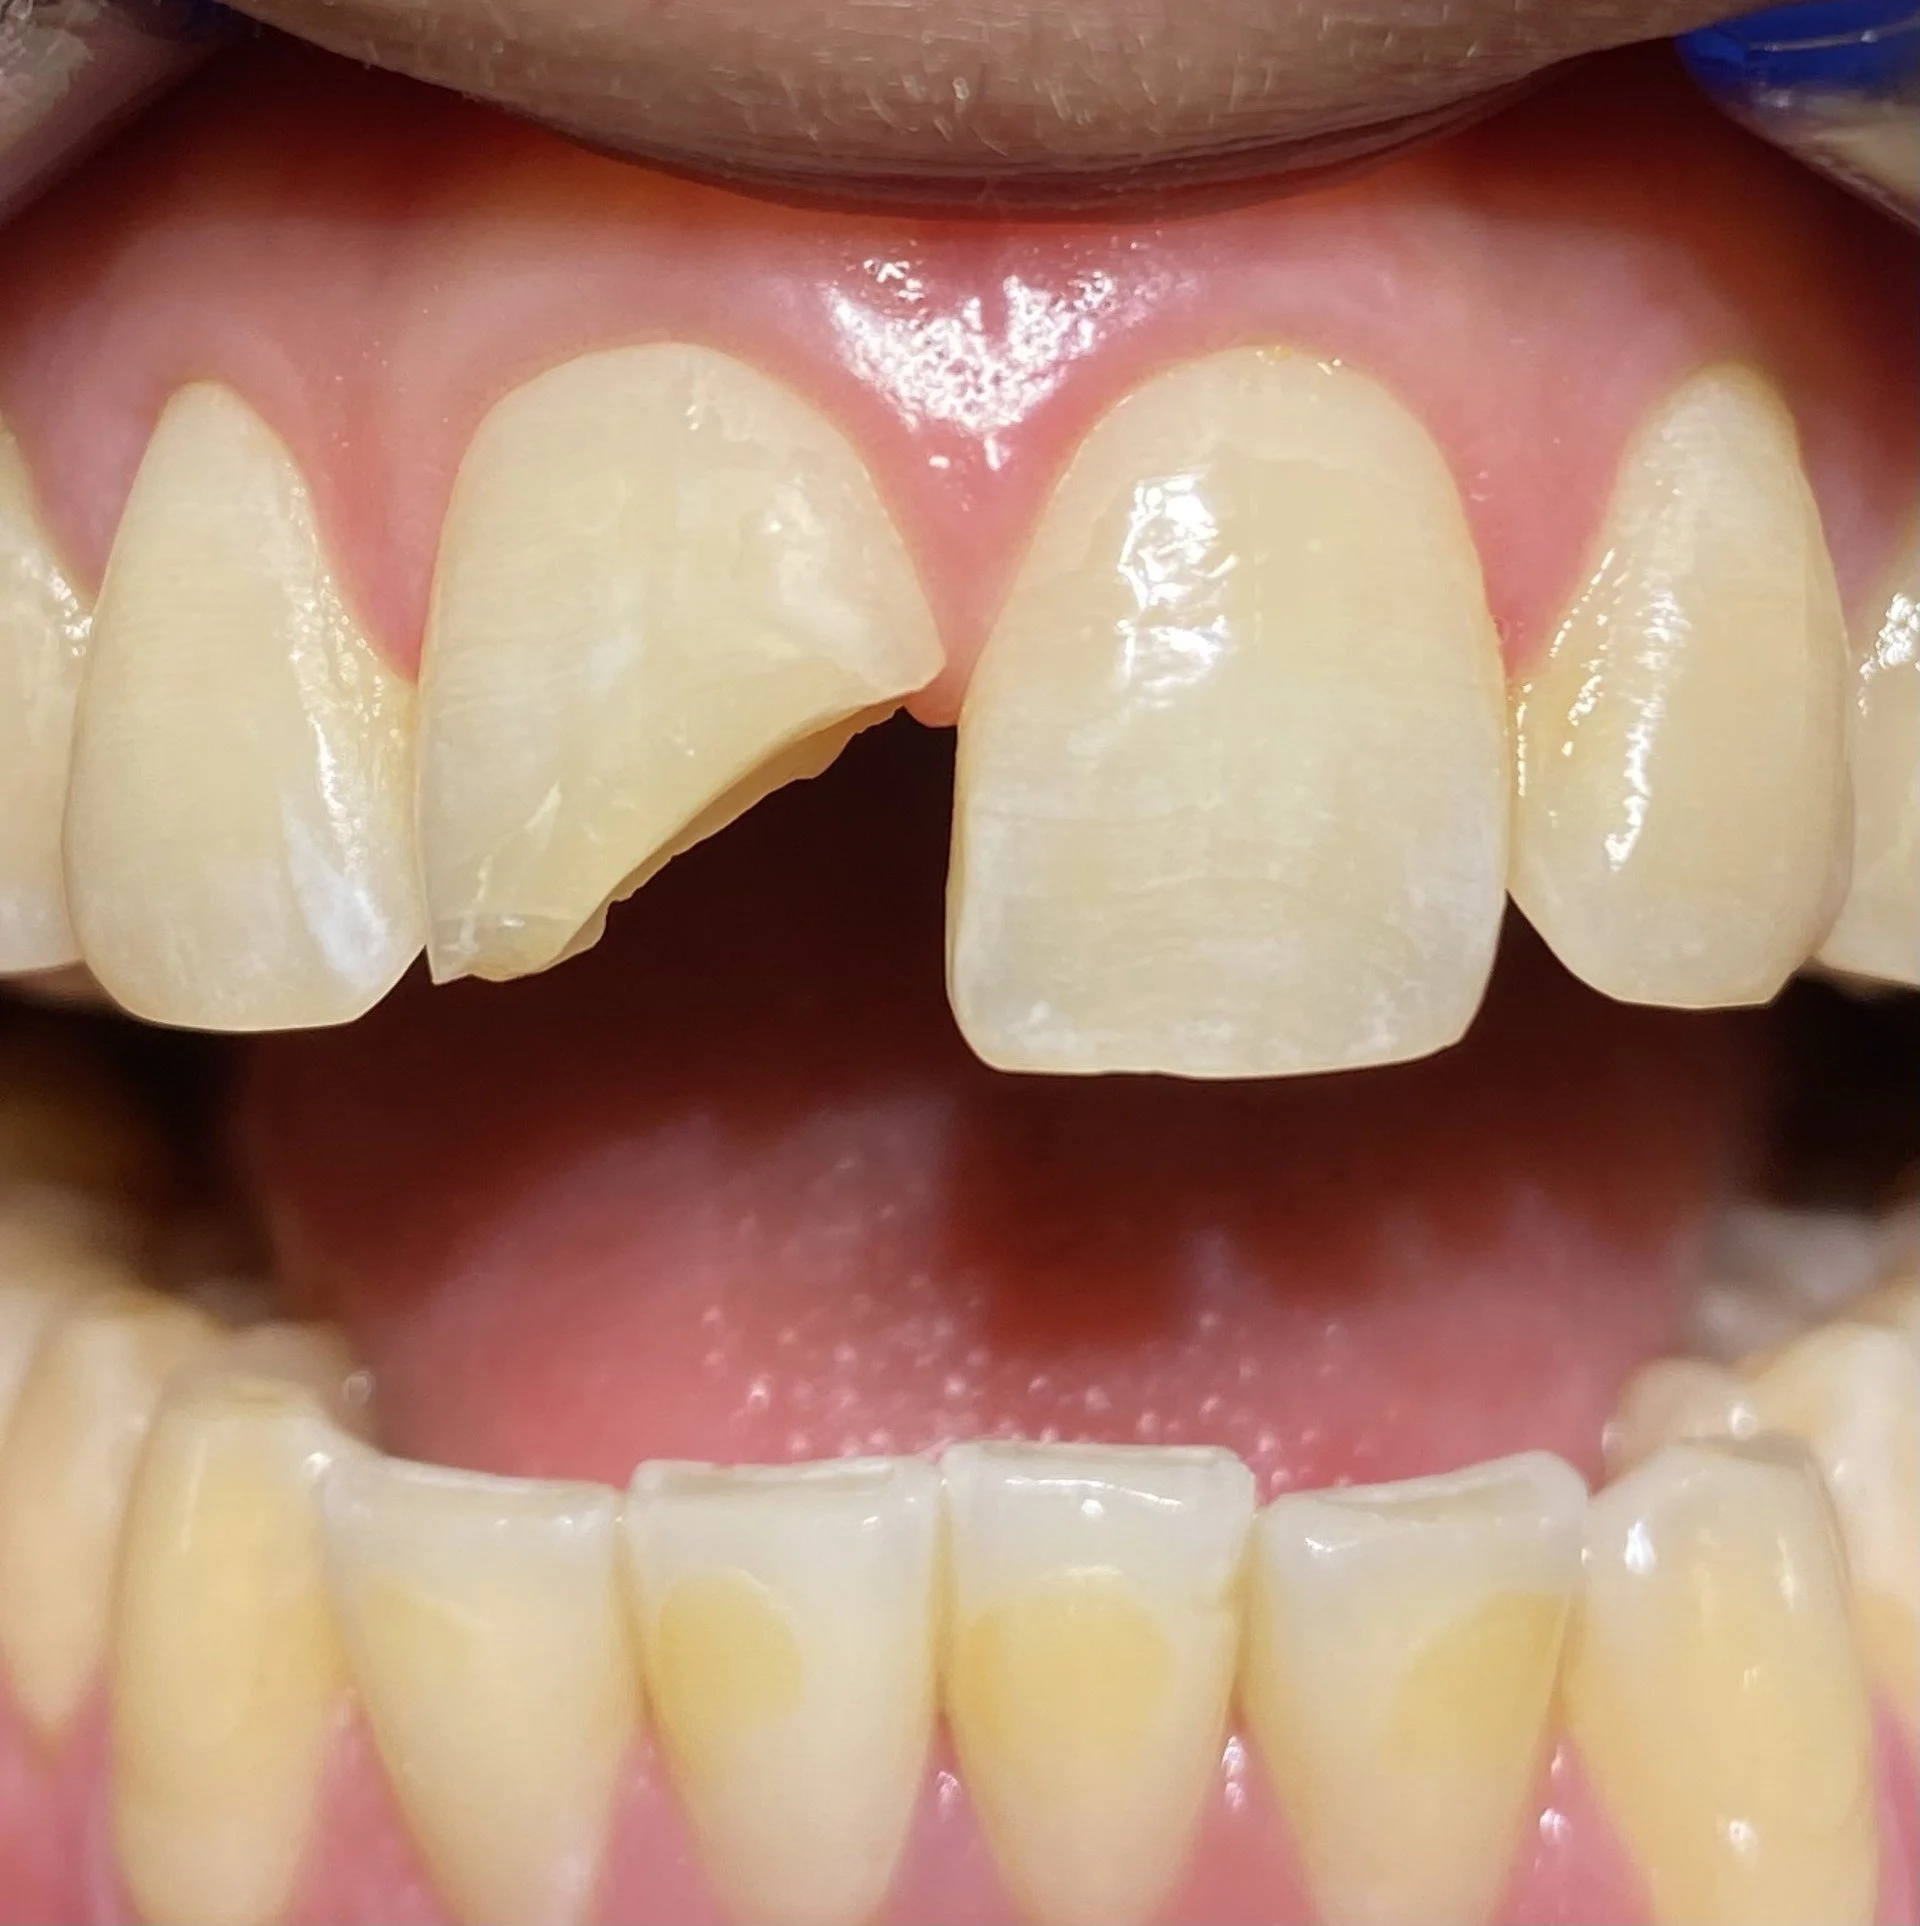

The completed case on the day of fitting and the gum is pale whitish in colour from the local anaesthetic.

This is the follow up in 2025